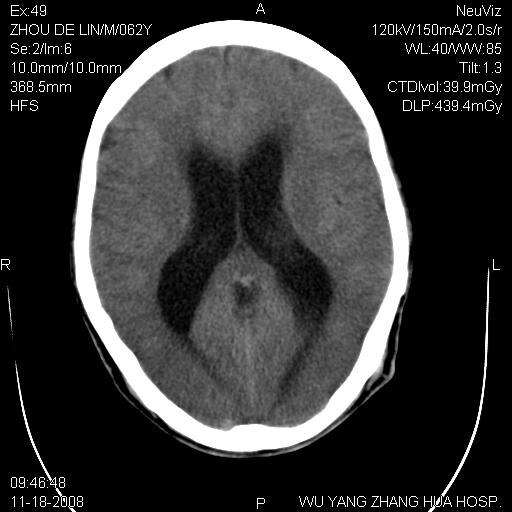

患者近段时间偶有头晕,无其他不适。既往有糖尿病病史。

小脑中线区见一类圆形混杂密度影,四脑室受压变形,其后方见一边界清楚的囊性低密度影,幕上脑室扩张。小脑中线区肿瘤,儿童多见于髓母细胞瘤,成人多见于胶质瘤。

诊断:小脑胶质瘤可能性大。建议增强扫描

支持,病灶似位于四脑室内,不除外四脑室室管膜瘤,发生几率也较高

小脑囊实性占位病变、脑室系统积水扩张、脑肿胀。

小脑囊实性占位病变、脑室系统积水扩张,建议增强

诊断:小脑胶质瘤可能性大。建议增强扫描。支持!

1)小脑蚓部(偏左侧)占位性病变;不排除转移瘤可能。建议行进一步检查。2)脑积水。